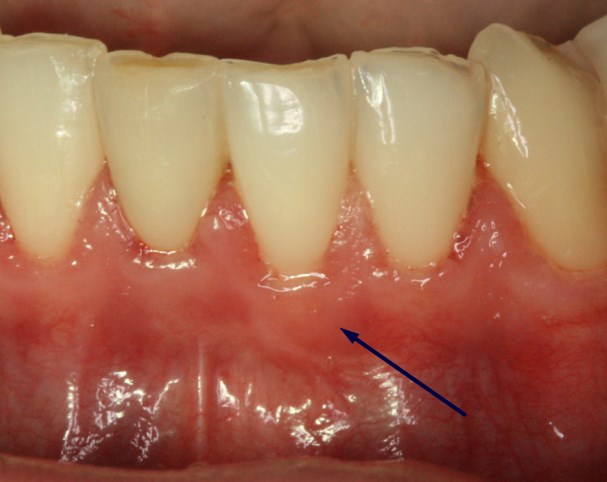

• Υψηλή θέση χαλινού: ο χαλινός είναι μια ινώδης πρόσφυση που είναι δυνατό να βρίσκεται πολύ κοντά στο άκρο του ούλου και να το "τραβάει", οδηγώντας σε υποχώρηση του ούλου. Η αφαίρεση του χαλινού αρκεί για τη σταθεροποίηση της κατάστασης και βελτίωση της υποχώρησης του ούλου.

Υποχώρηση ούλου εξαιτίας της παρουσίας του χαλινού

Αφαίρεση του χαλινού και βελτίωση της υποχώρησης του ούλου